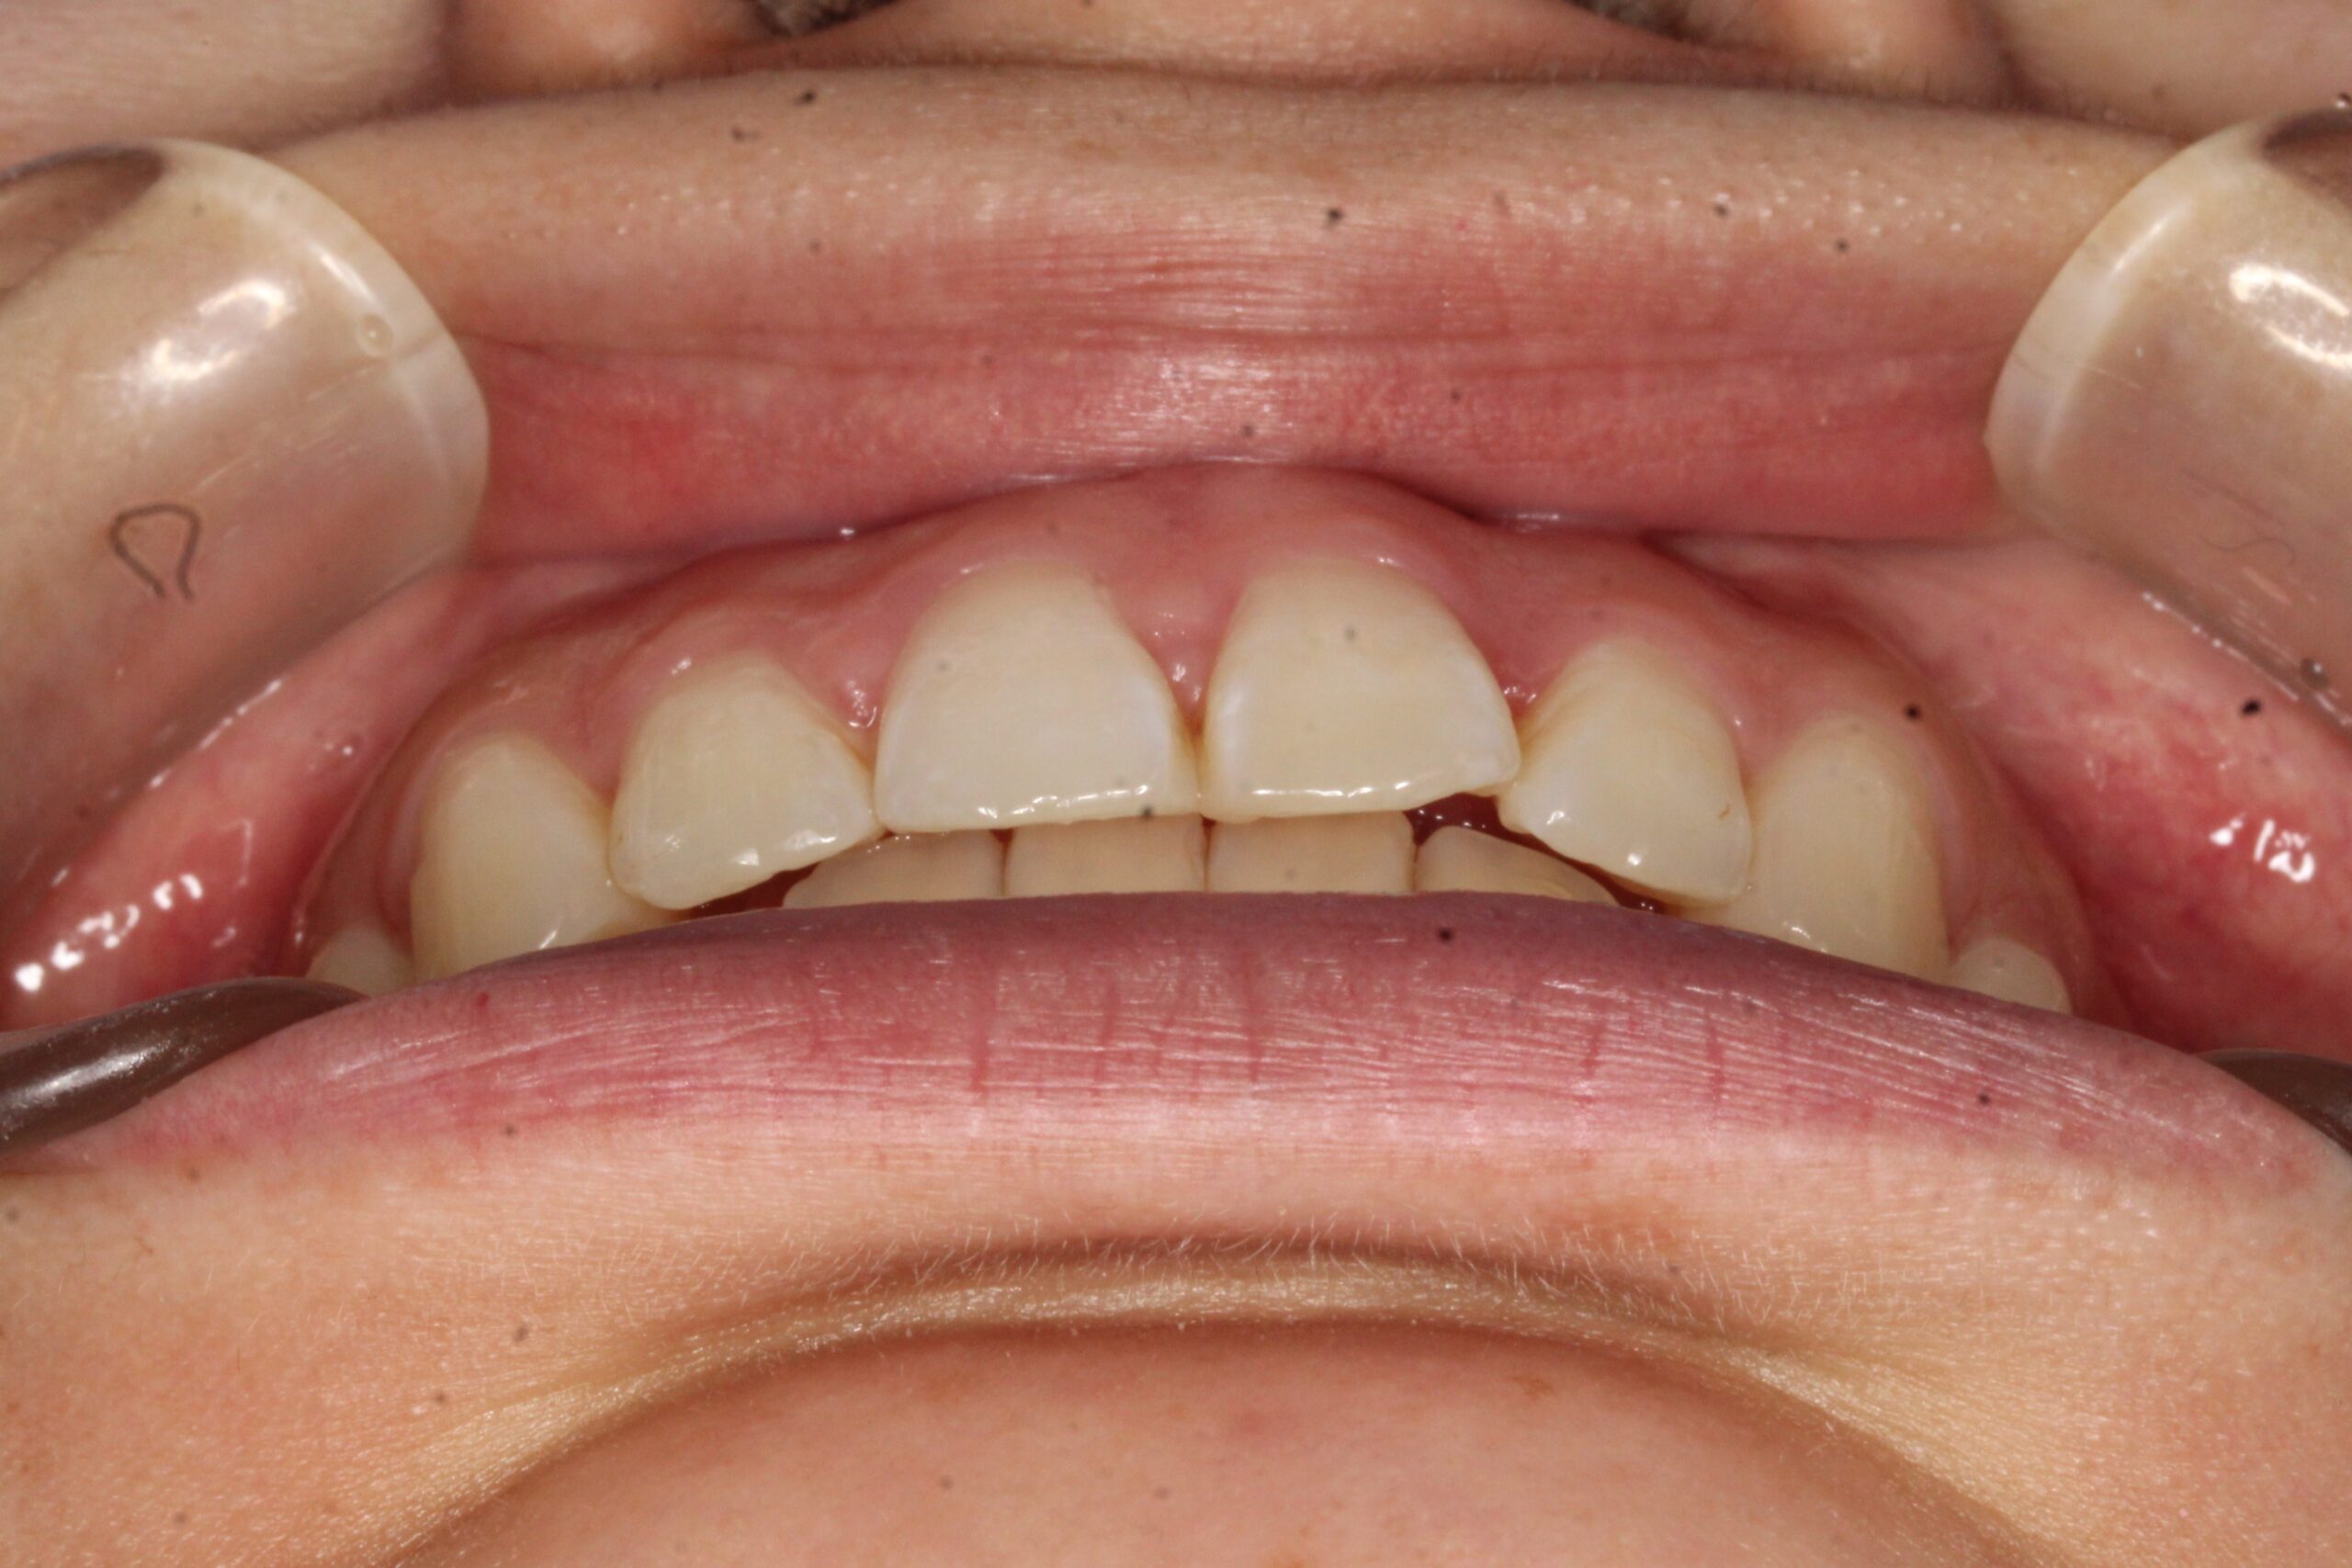

矯正術前:正面

矯正術後:正面